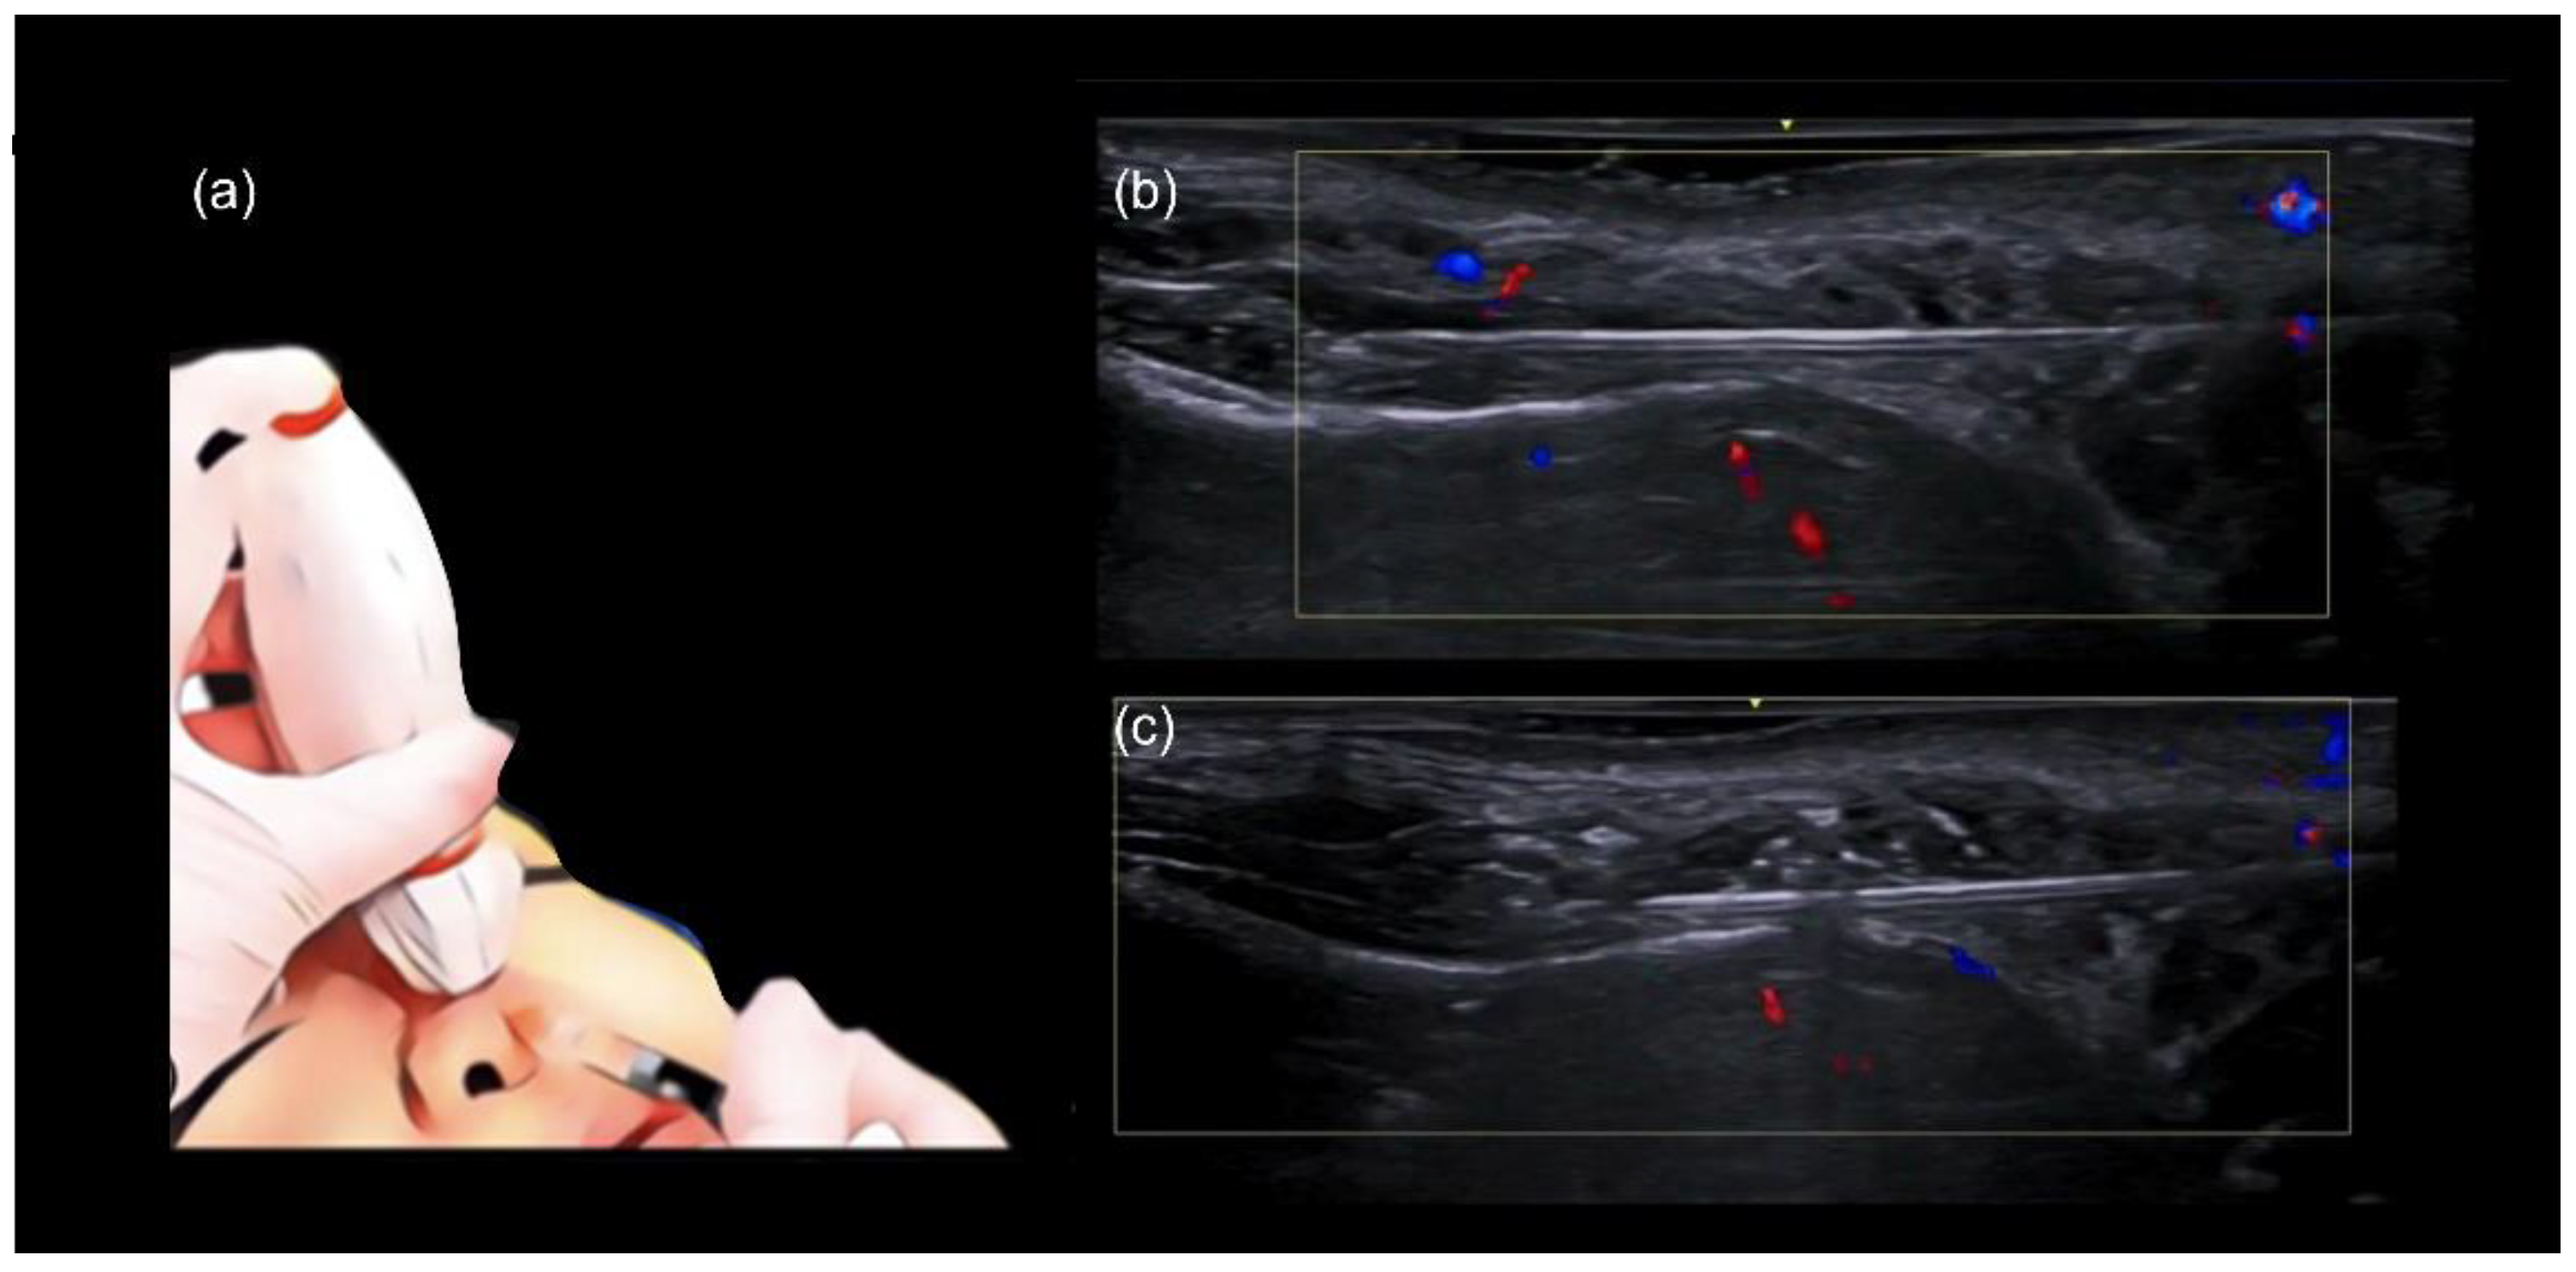

- Technique 1: Deep injections with a needle

- Technique 2: Deep injections with a cannula and ultrasound-guided filler placement